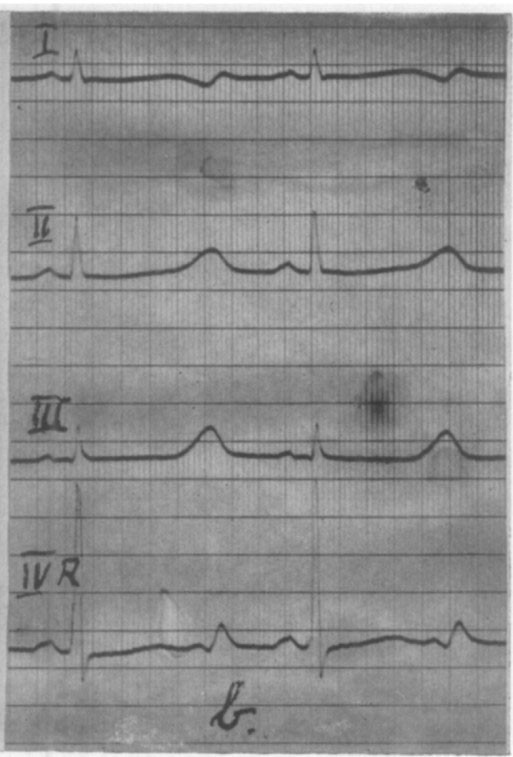

Under sykehusoppholdet i Tønsberg, som varte i fire uker, fant man heller ikke noe galt ved klinisk undersøkelse, røntgenundersøkelse av hjertet og diverse laboratorieprøver. Man påviste den samme forandringen i EKG (figur 4). Det ble ikke startet behandling (1, 21).

Jervell og Lange-Nielsens syndrom er et av de best kjente medisinske syndromene som har navn etter norske leger (1). Det er en livstruende arvelig kombinasjon av døvhet og forlenget QT-tid (2). QT-tiden måles i elektrokardiogrammet (EKG) fra starten av QRS-komplekset til slutten av T-bølgen, og avspeiler varigheten av hjertets sammentrekningsfase (systolen). Jo mer QT-tiden er forlenget, desto større er faren for hjerterytmeforstyrrelse i form av ventrikkeltakykardi, som kan gi besvimelser og i verste fall hjertedød. Til tross for oppdagelsens betydning er det ikke skrevet mye om dette syndromets historie. Hvem var legene som beskrev det første gang, hvordan arter det seg, hvordan ble det oppdaget og hvilke konsekvenser fikk oppdagelsen?